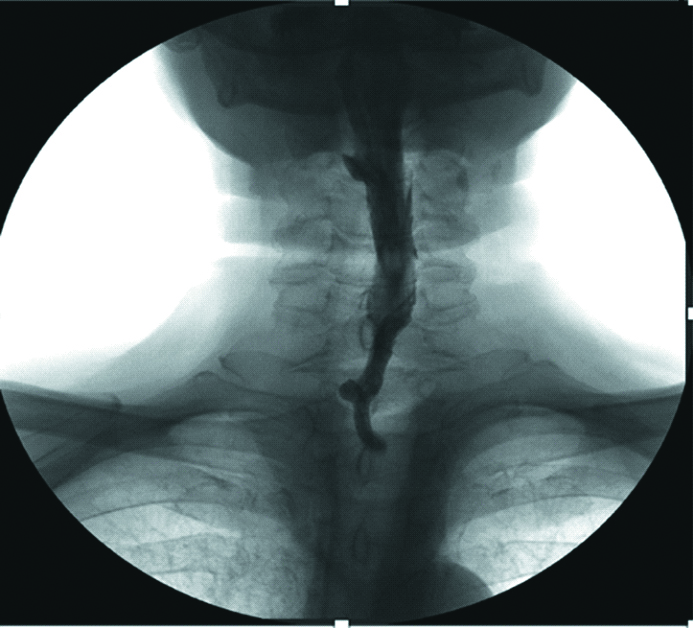

Control fluoroscopy of the cervical esophagus 4 months after the reconstructive stage did not detect filling defect or stenosis in the areas of the formed anastomoses between the pharynx and the flap or the esophagus and the flap (Figs. 8 and 9).

Figure 8. The X-ray image of the cervical esophagus. Front side

Рисунок 8. Рентгенография шейного отдела пищевода. Прямая проекция.